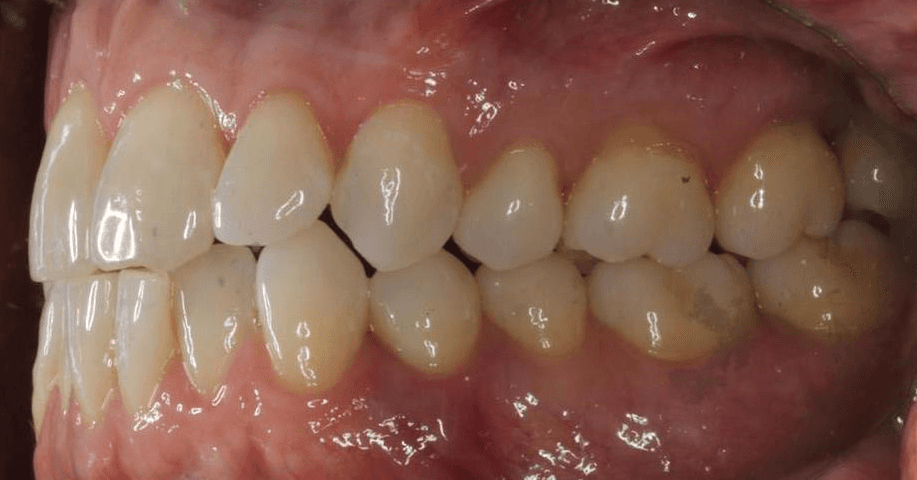

Initial treatment

INTRAORAL